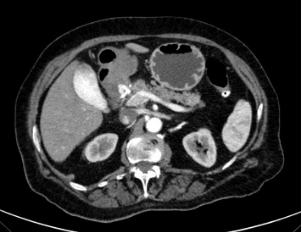

术后患者又出现两次呕血,生命体征保留,血红蛋白高于10 g/dl。手术后第一天,注射造影剂的CT扫描显示假性动脉瘤几乎完全消失。衣领处有一个约1厘米的小血管化斑点(图4)。患者保持稳定,没有新的呕吐发作,并通过CT扫描进行监测。

图4、CT扫描显示假性动脉瘤几乎完全消失,残留约1厘米的小血管化斑点

患者于术后第5天出院,出院后21天进行CT扫描,依诺肝素4000 IU/天治疗10天。随访时患者无症状,血液检查正常,血红蛋白稳定。CT扫描显示胃十二指肠动脉假性动脉瘤完全血栓形成,颈圈处未见残留补充征象(图5)。动脉瘤囊大小稳定。未发现肝脏或其他器官病变。没有安排进一步的后续行动。

图5、CT扫描显示胃十二指肠动脉假性动脉瘤完全闭塞,没有残留的补充迹象